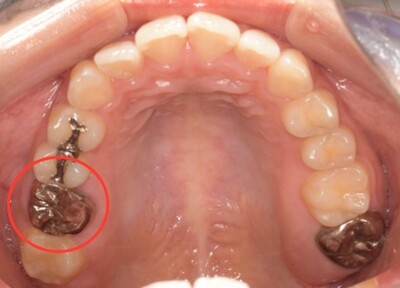

初診時口腔内写真

初診時パノラマX線写真と口腔内写真。

右上6に腫脹と排膿がみられた。